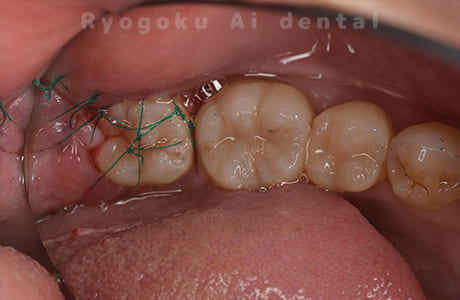

Case10

- 右下6番 重度カリエス

- 右下8を右下6へ移植に自家歯牙移植

- 約1か月半

- 220,000円

右下の銀歯が外れかかっているとのことでご来院された患者様です。虫歯が大きく、かつ歯が割れており、保存不可能と判断し、親知らずの移植を行いました。